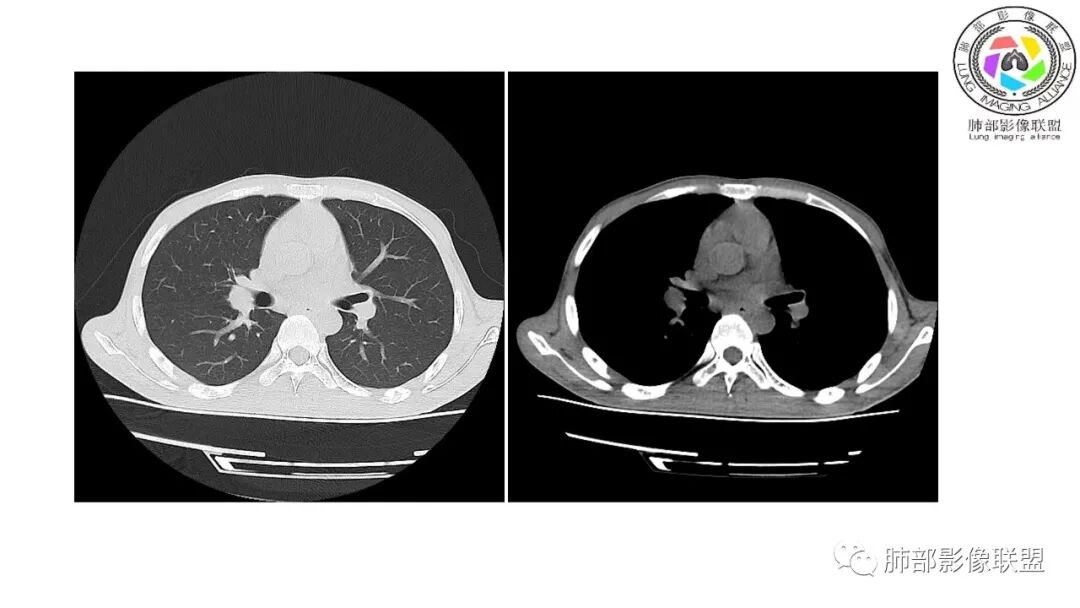

影像与临床:1.青年男性,HlV阳性,颜面部皮疹(未提供皮疹图像)、发热(高热),实验室CRP、PCT高,T-Spot阴性。2.右肺下叶空洞结节,壁厚不均,边界清楚,其内线状影,未见液平及钙化,未见卫星灶,纵隔淋巴结增大,双侧腋窝见增大淋巴结。心腔内低密度提示贫血可能。肝脾影增大,未见结节影及块影。腹膜后见多发增大淋巴结。

综合分析:本例肺部影像学改变并不具有特征性,空洞性病灶须与多种疾病鉴别,但年轻HIV阳性患者,高热,皮疹,肝脾增大,纵隔、腋窝、腹膜后见多发增大淋巴结等都强烈提示马尔尼菲篮状菌感染的可能性。